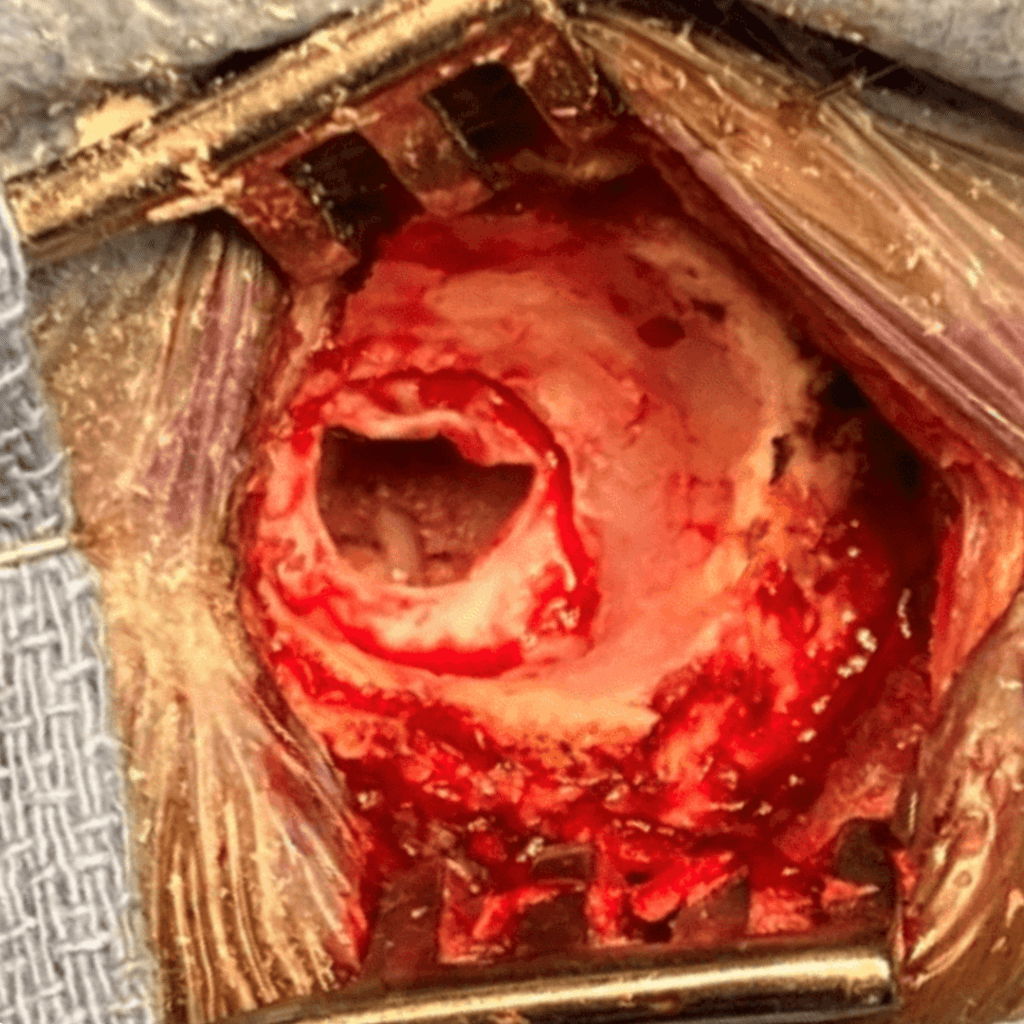

In my hands, the MVD usually takes about 2 hours once the operation has started. It is performed under general anesthesia, with the patient in the lateral position. Neuro-monitoring is performed throughout the case. A one-and-a-half-inch linear incision is made just behind the ear. A circular piece of bone is drilled out about the size of a quarter (Figure 1). The dura is opened up to the transverse – sigmoid sinus junction, and cerebrospinal fluid is released until the brain is fully relaxed (Figure 2). The microscope is brought in to provide both excellent lighting and magnification. Arachnoid dissection is performed so the vascular conflict against the nerve can be clearly visualized. Sometimes, the endoscope can also be used to clarify the anatomy.

In this case, a loop of the superior cerebellar artery was causing significant compression and distortion of the trigeminal nerve root (Figure 3). The superior cerebellar artery is the usual offending blood vessel in cases of trigeminal neuralgia. Using micro-dissection techniques with appropriate micro -instruments, the artery is dissected off the nerve, and very small pieces of teflon felt (a non-absorbable material) are used to keep the artery from recompressing the nerve. The final image under the microscope shows the trigeminal nerve root fully decompressed, with resumption of normal anatomy (Figure 4).